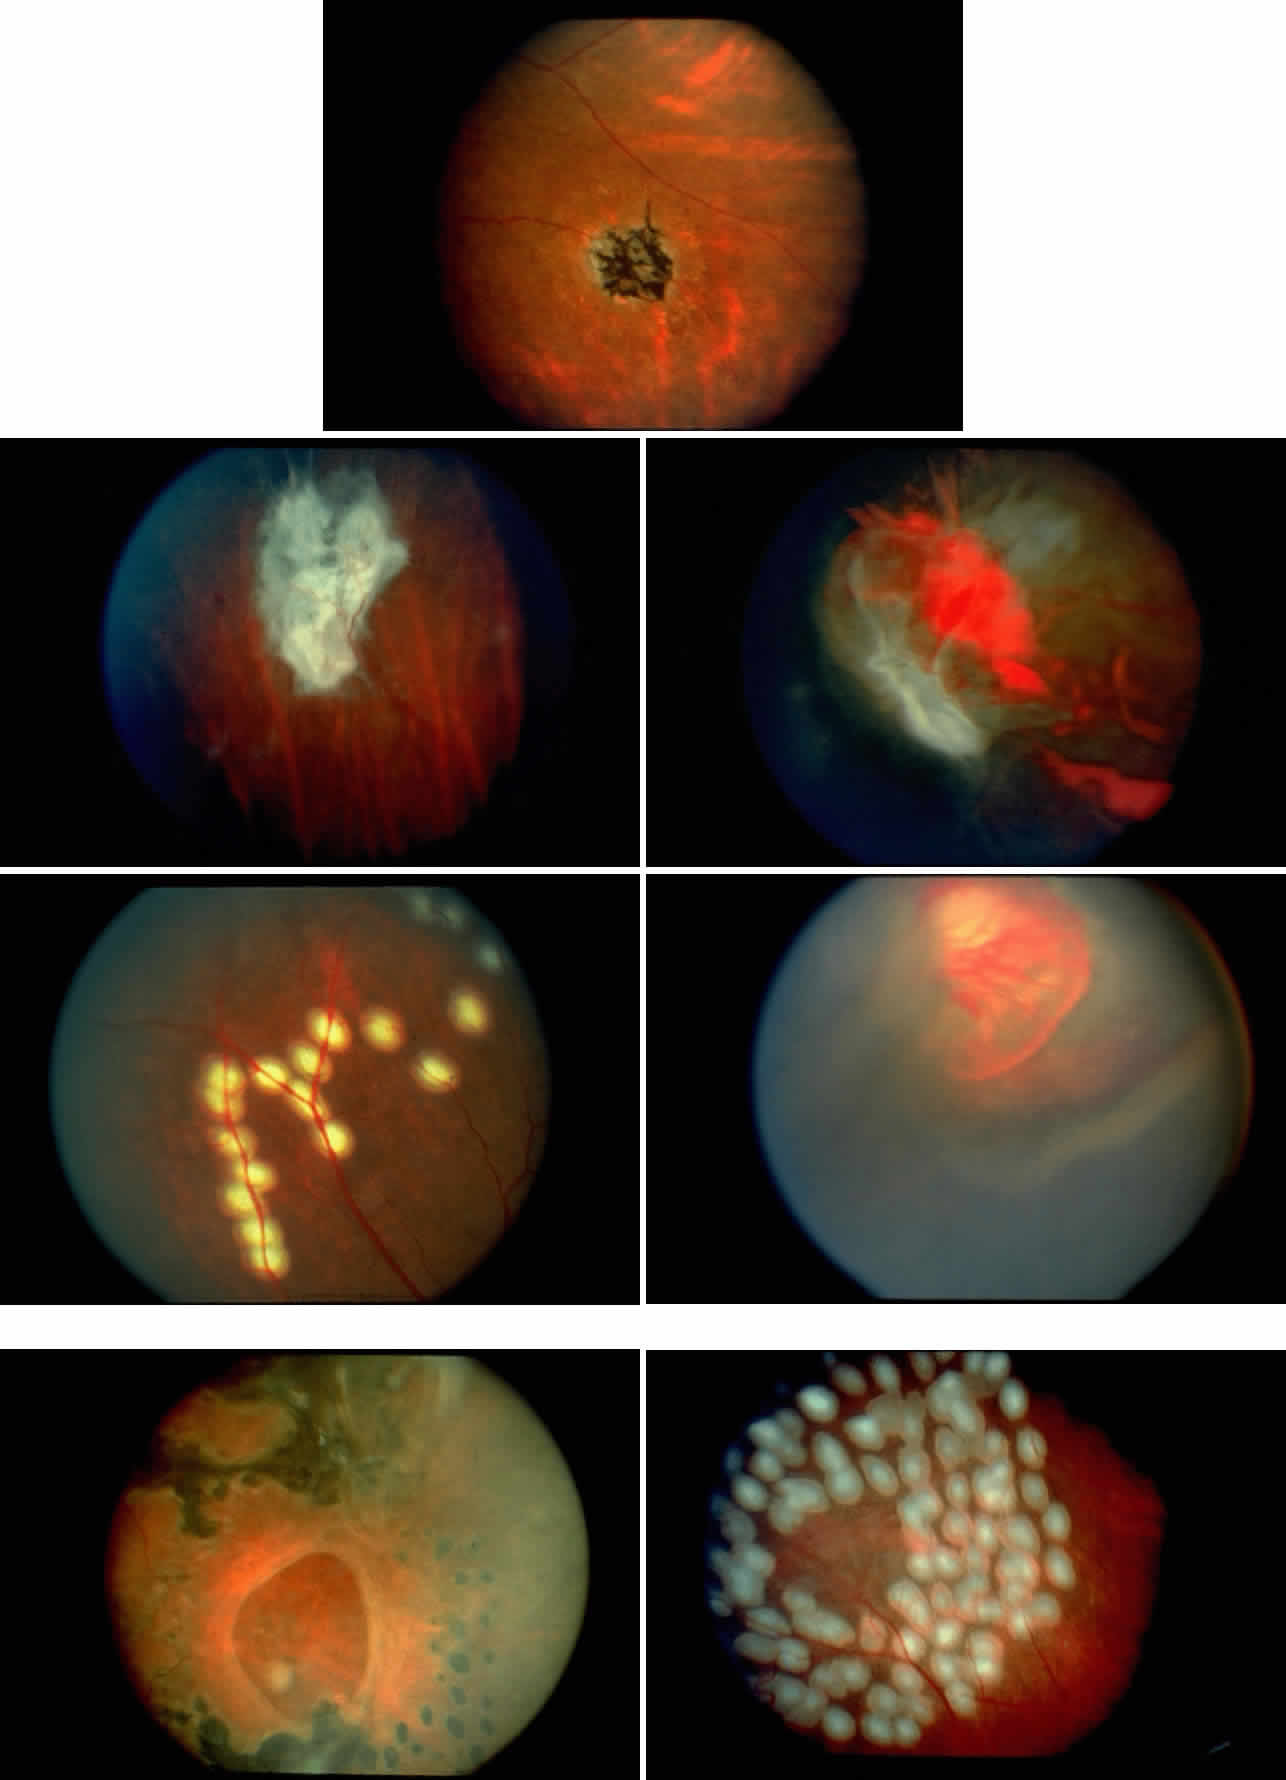

STAGE II: PERIPHERAL ARTERIOLAR-VENULAR ANASTOMOSES. Following occlusion of the terminal arterioles, anastomotic channels form to channel the blood from the occluded arteriole to the nearest venules. These anastomoses form at the interface between the perfused and nonperfused retina. Most likely, they are dilated preexisting capillaries rather than new vessels, since they do not leak on fluorescein angiography. The redirection of blood flow is probably due to hydrostatic forces (Figs. 22 and 23).

|

STAGE III: PRERETINAL NEOVASCULARIZATION (PROLIFERATIVE SICKLE RETINOPATHY). “Sea fan”-shaped neovascularization typically develops on the venular side of an arteriolar-venular anastomosis, mimicking the normal development of retinal capillaries (Fig. 24).125 A lowered oxygen tension and angiogenic factors released on the venular side may be the stimulus for neovascular growth.125,126 In most instances, the direction of growth is toward the ora serrata, from the perfused retina toward the nonperfused retina. Presumably, this represents an abortive attempt to revascularize the nonperfused retina, initiated by vasoproliferative factors.

The characteristic neovascular lesions of PSR are called sea fans because they resemble the marine invertebrate Gorgonia flabellum.70 They tend to occur more commonly in the temporal periphery, but they have been reported to occur in the temporal macula in the presence of extensive nonperfusion.130,133 Initially they grow on the surface of the retina, but they often become elevated into the vitreous and adhere to a partially detached posterior hyaloid.114 It may be difficult to visualize small sea fans ophthalmoscopically; however, fluorescein angiography clearly demonstrates leakage of dye into the vitreous (Fig. 25). The feeding arteriole is usually more tortuous than the draining venule (Fig. 26). Early on, the neovascular lesion is fed by a single arteriole and drained by a single venule, but with time, additional arterioles and venules become arborized within the lesion (Fig. 27).129 Growth of the sea fan often occurs circumferentially, rather than radiallyÜmh- 1Ý, toward the ora serrata. Progressive circumferential growth may lead to neovascular lesions extending around the entire periphery. As it matures, a white fibroglial mantle often covers the neovascular tissue (Color Plate 2B).

|

|

PSR is associated with the severe vision-threatening sequelae of sickle cell disease: vitreous hemorrhage (stage IV) and retinal detachment (stage V). These stages are believed to result from transudation of blood components into the vitreous through the incompetent neovascular tissue (Fig. 28). Vitreous fluorophotometry has quantified the leakage from the peripheral neovascularization.134 This leads to premature syneresis and collapse of the vitreous, inducing tractional forces on the retina that lead to vitreous hemorrhage, retinal tears, and tractional and rhegmatogenous retinal detachment. In rare cases, an exudative detachment may occur.

|

STAGE IV: VITREOUS HEMORRHAGE. Vitreous hemorrhage often complicates PSR. In a selected series of patients with untreated SC disease, vitreous hemorrhage was found in 28% at diagnosis and in 44% after 31 months.130 In the presence of neovascularization, the three risk factors for the development of vitreous hemorrhage include SC disease, more than 60° of perfused sea fans, and the presence of old blood in the eye.139 In a long-term follow-up of an untreated control group participating in a randomized clinical trial of feeder vessel photocoagulation for PSR, vitreous hemorrhage occurred in 45% of eyes and was recurrent in two thirds of these eyes.140

Transudation of plasma results in vitreous syneresis and fibrosis and induces collapse of the formed vitreous, which causes traction on the adherent neovascular tissue. The fragile elevated vessels in the neovascular membranes are prone to rupture, resulting in hemorrhage.141 The hemorrhage is frequently localized in the periphery near the sea fan, but diffuse hemorrhage does occur and may obscure fundus details (Color Plate 2C).

STAGE V: RETINAL DETACHMENT. Vitreous traction on the retina may cause tractional retinal detachments or retinal breaks that can result in localized or total rhegmatogenous retinal detachments.131,142 The retinal breaks are usually found adjacent to neovascular tissue and may be difficult to detect because of overlying hemorrhage. Exudative retinal detachments may occur in rare cases and reportedly have resolved after photocoagulation of the neovascularization.143